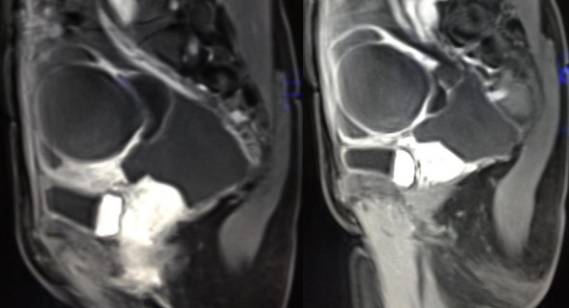

女性,42岁。

主诉:下腹部胀痛不适1月余

病史:自诉13岁时患“结核”,8年前行“左侧附件包块”切除术。

病理结果:黄体血肿

黄体血肿为正常排卵过程中,卵泡层破裂,引起出血,较多的血液潴留在卵泡或黄体腔内形成血肿。

正常黄体直径为15mm左右,以后转变为白体,并在下一个周期的卵泡期自然消退。若黄体内出血量较多,则形成黄体血肿,或称黄体内出血,出血性黄体。黄体血肿多为单侧,一般直径为40mm,偶可达100mm,黄体血肿被吸收后可导致黄体囊肿,较大的血肿破裂时可出现腹腔内出血,剧烈腹痛、少量阴道流血和腹膜刺激征,不易与宫外孕区别。

根据时间不同MR信号也有所不同,TIWI脂肪抑制序列可以鉴别脂肪和出血。